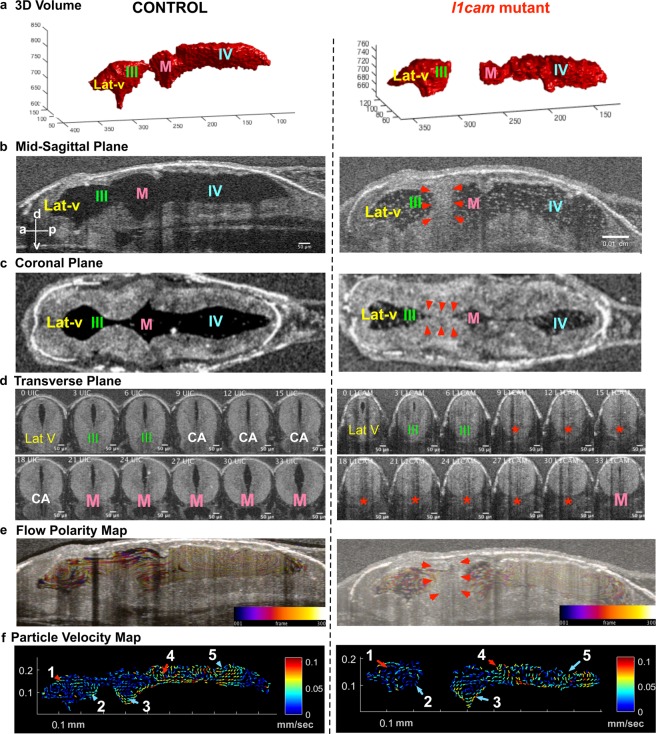

Figure 4. F0 CRISPR mutation in L1CAM causes cerebral aqueduct stenosis. The left column shows control and right column shows l1cam F0 CRISPR mutant images for all panels. (a) 3D rendering of the tadpole ventricular system shows aqueductal stenosis and a smaller ventricular system in l1cam F0 CRISPR mutant. (b) Mid sagittal view and (c) Coronal view of control and l1cam F0 CRISPR mutant, the later showing stenosis of the cerebral aqueduct (red arrowheads). (d) Transverse view of the control and l1cam F0 CRISPR mutant, starting at the end of the lateral ventricle through the cerebral aqueduct and ending in the midbrain ventricle. Control embryo shows normal opening of the duct whereas the mutant shows complete blockage (red star). (e) Relatively normal ciliary flow fields in the control and mutant animals. (f) 2D Particle Velocity Map shows intact FFs 1-5. (Lat-V: lateral ventricle, III: 3rd ventricle, M: Midbrain ventricle, IV: 4th ventricle).